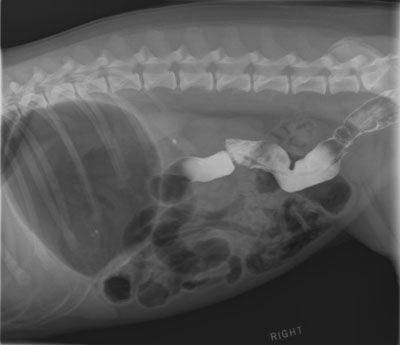

Figure 1 - Right Lateral Abomen